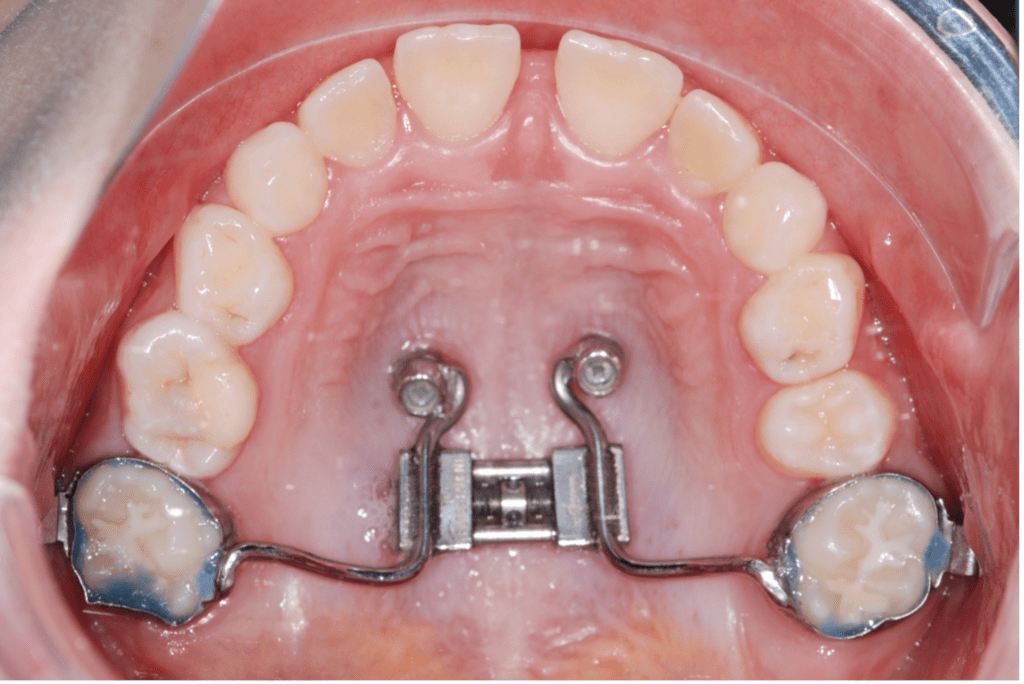

Hyrax expander cemented on the upper first molars and premolars Hyrax Expander Instructions The appliance that the doctor placed today is called a hyrax/pendex. A palatal expander (hyrax appliance) is a device used to widen the upper jaw when it is narrow. This makes room for the teeth and helps. A tiny screw in the center is. Hyrax expander is a dental appliance used to widen the narrow space of your upper jaw.. Hyrax Expander Instructions.

Hyrax expander cemented on the upper first molars and premolars Hyrax Expander Instructions The appliance that the doctor placed today is called a hyrax/pendex. Hyrax expander is a dental appliance used to widen the narrow space of your upper jaw. A palatal expander (hyrax appliance) is a device used to widen the upper jaw when it is narrow. It is normal for the expander to create a small space between your front teeth. Hyrax Expander Instructions.